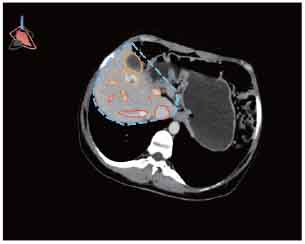

CT-Ultrasound Fusion in PCNL

3D CT reconstruction

CT-Ultrasound real-time fusion

3D navigation and tracking